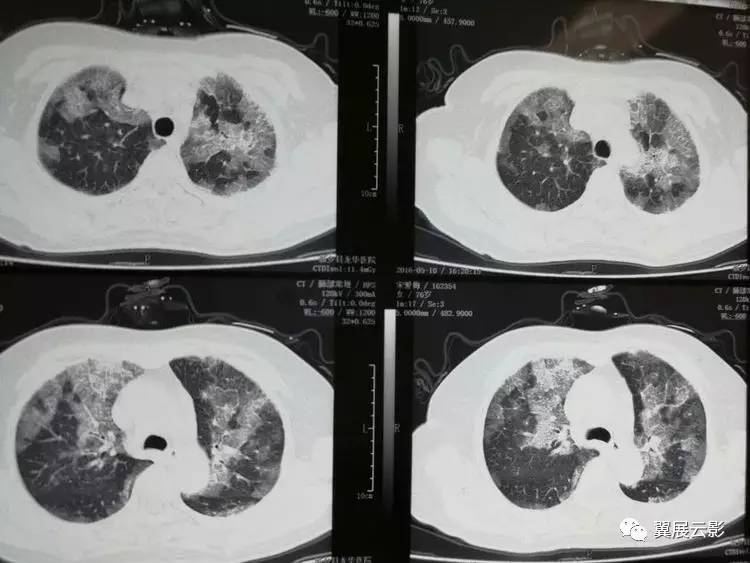

肺蛋白沉积,听起来似乎是一种与老年人相关的疾病,但事实上,它并不限于年龄。它可能影响任何年龄段的人,给他们的生活带来极大的困扰和痛苦。

我记得有一次,在实习的时候,我遇到了一个患有肺蛋白沉积的患者。他是一个年轻人,只有三十多岁,但是因为这个疾病,他的生活已经完全被打乱了。他常常呼吸困难,整夜难以入眠,白天也因为疲惫而无法正常工作。看着他那双因为疾病而黯淡无光的眼睛,我感受到了巨大的愧疚和无能为力。

肺蛋白沉积并不是一种普通的感冒,也不是一种轻易可以治愈的疾病。它需要长期的治疗和康复,而有些情况下,甚至可能需要手术干预。对于患者来说,这意味着巨大的经济负担和身心煎熬。而对于医生来说,这更是一种巨大的挑战和责任,我们必须竭尽所能,帮助每一个患者度过难关。